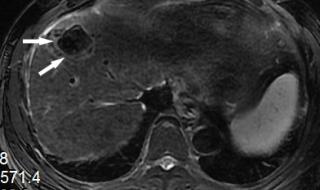

原发性肝癌,又叫肝癌,是肝脏细胞或肝内胆管上皮细胞发现的恶性肿瘤。肝脏发现肿瘤,可以是肝脏本身产生的,也可以是其他部位转移而来的。如果比如胃癌转移到肝脏,叫胃癌肝转移。原发性肝癌在我们最常见的是慢性肝炎导致肝硬化,发展成原发性肝癌。